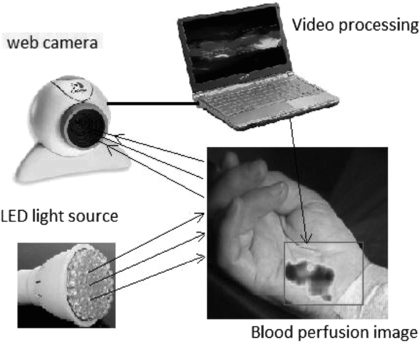

The detector technology usually comprises a high sensitivity CMOS camera which is held at a fixed distance, e.g. 10–20 cm from the tissue, to measure the variations in light (typically 2–5% of overall reflected light). Images can be collected at rates of tens of frames per second (fps), enabling the pulsatile components to be extracted without aliasing. Image processing comprises various stages, including band-pass filtering and averaging of regions of interest (ROI). The time-varying intensity modulation is strongly affected by relative movement of the camera and body so image processing methods are used to reduce the effect of motion artefacts e.g. by averaging of pixels or Fourier analysis techniques (Wieringa et al 2005, Verkruysse et al 2008). Other centres have experimented with lock-in amplifiers to improve the signal-to-noise ratio (Kamshilin et al 2011). The sensitivity of modern systems allows measurements to be made using very low cost webcams and distances from camera to measurement surface can now typically be 1 m (Rubins et al 2011) (figure 17).

Figure 17. iPPG system comprising light source (4 W bulb of 80 white LEDs) and standard web camera with image processing performed on a laptop computer. The system can acquire images at 15 fps with resolution 640×480 to calculate blood perfusion changes in real-time (permission granted to re-use from Rubins et al 2011 IFMBE Proceedings vol 34 (Berlin: Springer) pp 183–6).